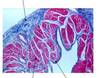

How to distinguish cardiac muscle cells

striations

intercalated discs

branched fibers

centrally located nuclei

How to distinguish myocardium

- cardiac muscle cells

- strands of connective tissue and vascular elements course through the myocardium between the fascicles

Cardiac muscle cells contents

- contractile proteins

- Sarcoplasmic reticulum

- T-tubules

- High density of mitochondria (40% of cytoplasmic volume)

Cardiac muscle cells have specialized junctions called

intercalated discs

Intercalated discs functional components

3 listed

- desmosomes - hold the cells together under the forces of contraction

- adherens junctions - hold the cells together under the forces of contraction

- gap junctions - facilitate the movement of signals to contract from one cell to another